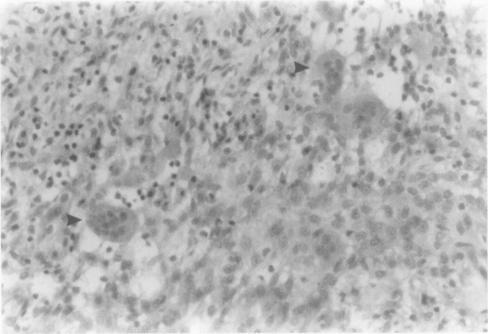

To determine the cytochemical and functional phenotype of multinucleated giant cells in pigmented villo nodular synovitis (PVNS).

Giant cells isolated from a patient with PVNS of the knee were assessed for a number of markers used to distinguish osteoclasts from macrophages/ macrophage polykaryons: evidence of tartrate resistant acid phosphatase (TRAP) activity; expression of CD11b, CD14, CD51, and calcitonin receptors; and the ability of the giant cells to carry out lacunar resorption.

Isolated giant cells expressed an osteoclast antigenic phenotype (positive for CD51, negative for CD11b and CD14) and were TRAP and calcitonin receptor positive. They also showed functional evidence of osteoclast differentiation, producing numerous lacunar bone resorption pits on bone slices in short term culture.

The giant cells in this case of PVNS express all the phenotypical features of osteoclasts including the ability to carry out lacunar resorption. This may account for the bone destruction associated with this aggressive synovial lesion.